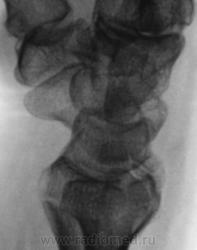

Контур нечеткий, склероз и т.д.-на перелом не схоже. А действительно локальная болезненность в латер. лодыжке?

Да, болезненность есть, клинически хирурги - за перелом.

Краевой перелом Наружной лодыжки